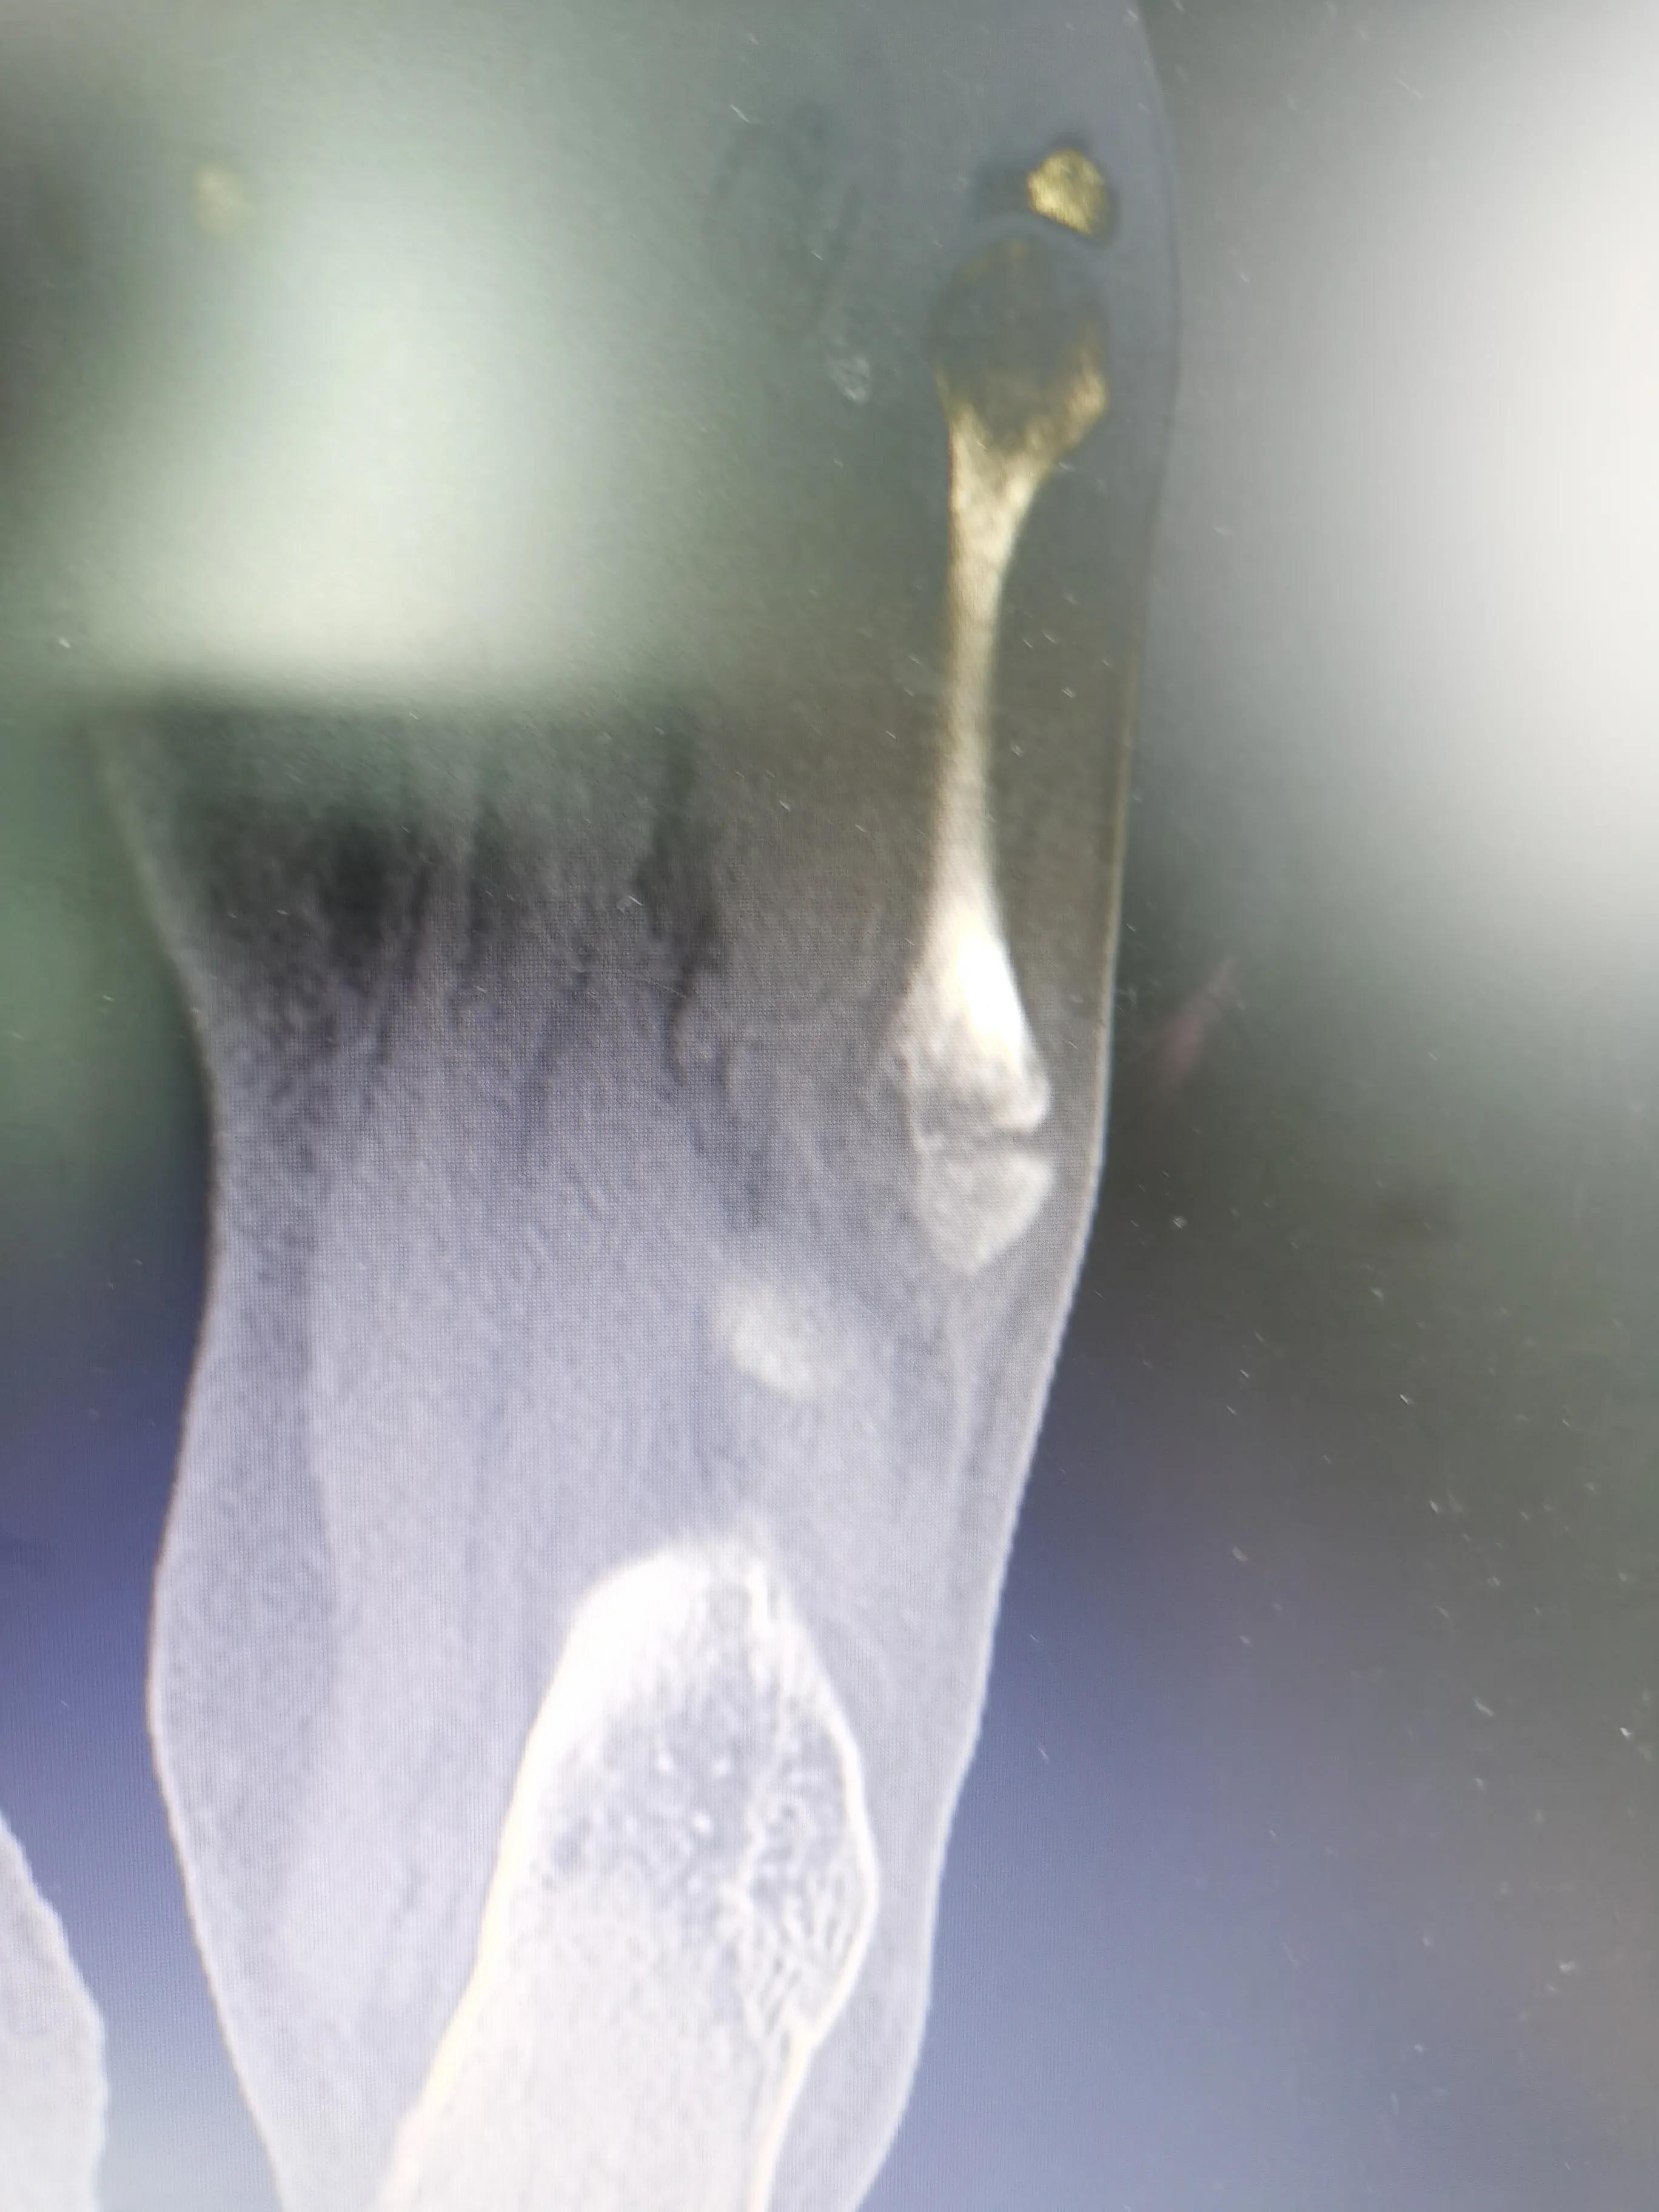

这是CT诊断书

医生提出手术治疗。由于要申报工伤,社保在深圳,最好转深圳方便报销,所以同事在6.9就安排帮忙转院到深圳公司附近一家医院